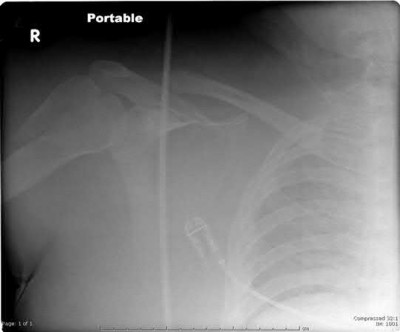

A 64-year-old woman is thrown off a horse, sustaining the injury shown in Figures A and B. She undergoes surgical fixation as seen in Figures C through E. What is the most commonly reported complication of this procedure?

The patient in the scenario has a 2-part proximal humerus fracture treated with a locking plate as seen in Figures A-E. The most common complication with the use of this implant is screw penetration. The terms screw cut out and penetration are often used interchangeably in the literature with cut out appearing more frequently in reports regarding intertrochanteric fractures.

Owsley et al retrospectively reviewed 53 proximal humerus fractures treated with locking plates and the same post-operative protocol. The most common complication was screw cut out or penetration, followed by varus displacement. They concluded that 3 and 4-part fractures in patients over 60 years have a higher incidence of failure.

Agudelo et al retrospectively reviewed 153 patients at a level-one trauma center treated with proximal humerus locking plates, investigating modes of failure for the implant. They determined that varus malreduction (head-shaft angle